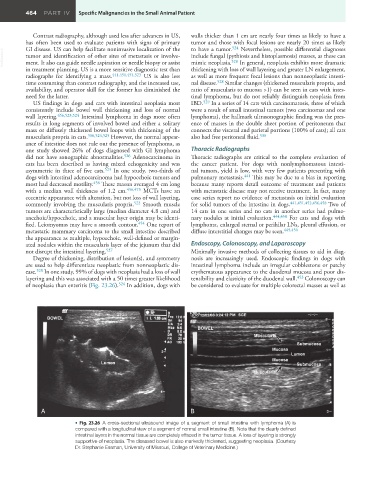

ease. 528 In one study, 99% of dogs with neoplasia had a loss of wall erythematous appearance to the duodenal mucosa and poor dis-

layering and this was associated with a 50 times greater likelihood tensibility and elasticity of the duodenal wall. 453 Colonoscopy can

of neoplasia than enteritis (Fig. 23.26). 524 In addition, dogs with be considered to evaluate for multiple colorectal masses as well as

• Fig. 23.26 A cross-sectional ultrasound image of a segment of small intestine with lymphoma (A) is

compared with a longitudinal view of a segment of normal small intestine (B). Note that the clearly defined

intestinal layers in the normal tissue are completely effaced in the tumor tissue. A loss of layering is strongly

supportive of neoplasia. The diseased bowel is also markedly thickened, suggesting neoplasia. (Courtesy

Dr. Stephanie Essman, University of Missouri, College of Veterinary Medicine.)